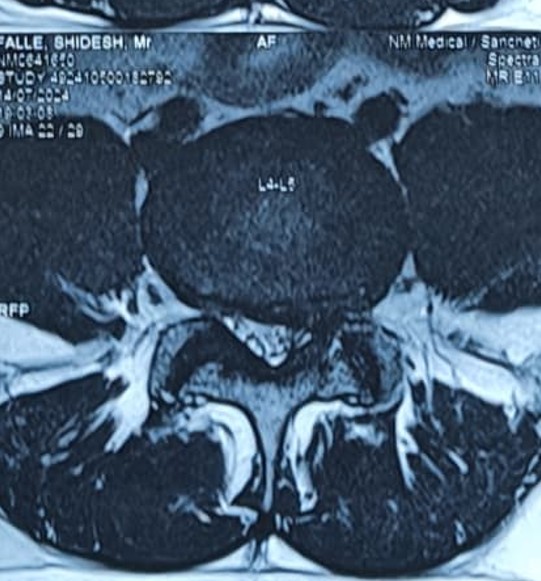

When the space in your lower back (lumbar spinal canal) gets narrow, nerves can get pinched. This often makes it hard to walk for long, and you may feel pain or numbness in your legs.